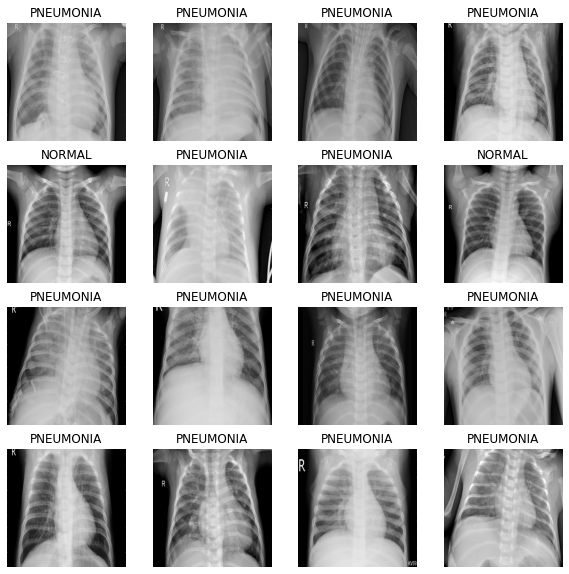

# 이미지 배치를 입력하면 여러장의 이미지를 보여줍니다.

def show_batch(image_batch, label_batch):

plt.figure(figsize=(10,10))

for n in range(BATCH_SIZE):

ax = plt.subplot(4,math.ceil(BATCH_SIZE/4),n+1)

plt.imshow(image_batch[n])

if label_batch[n]:

plt.title("PNEUMONIA")

else:

plt.title("NORMAL")

plt.axis("off")

image_batch, label_batch = next(iter(train_ds))

show_batch(image_batch.numpy(), label_batch.numpy())